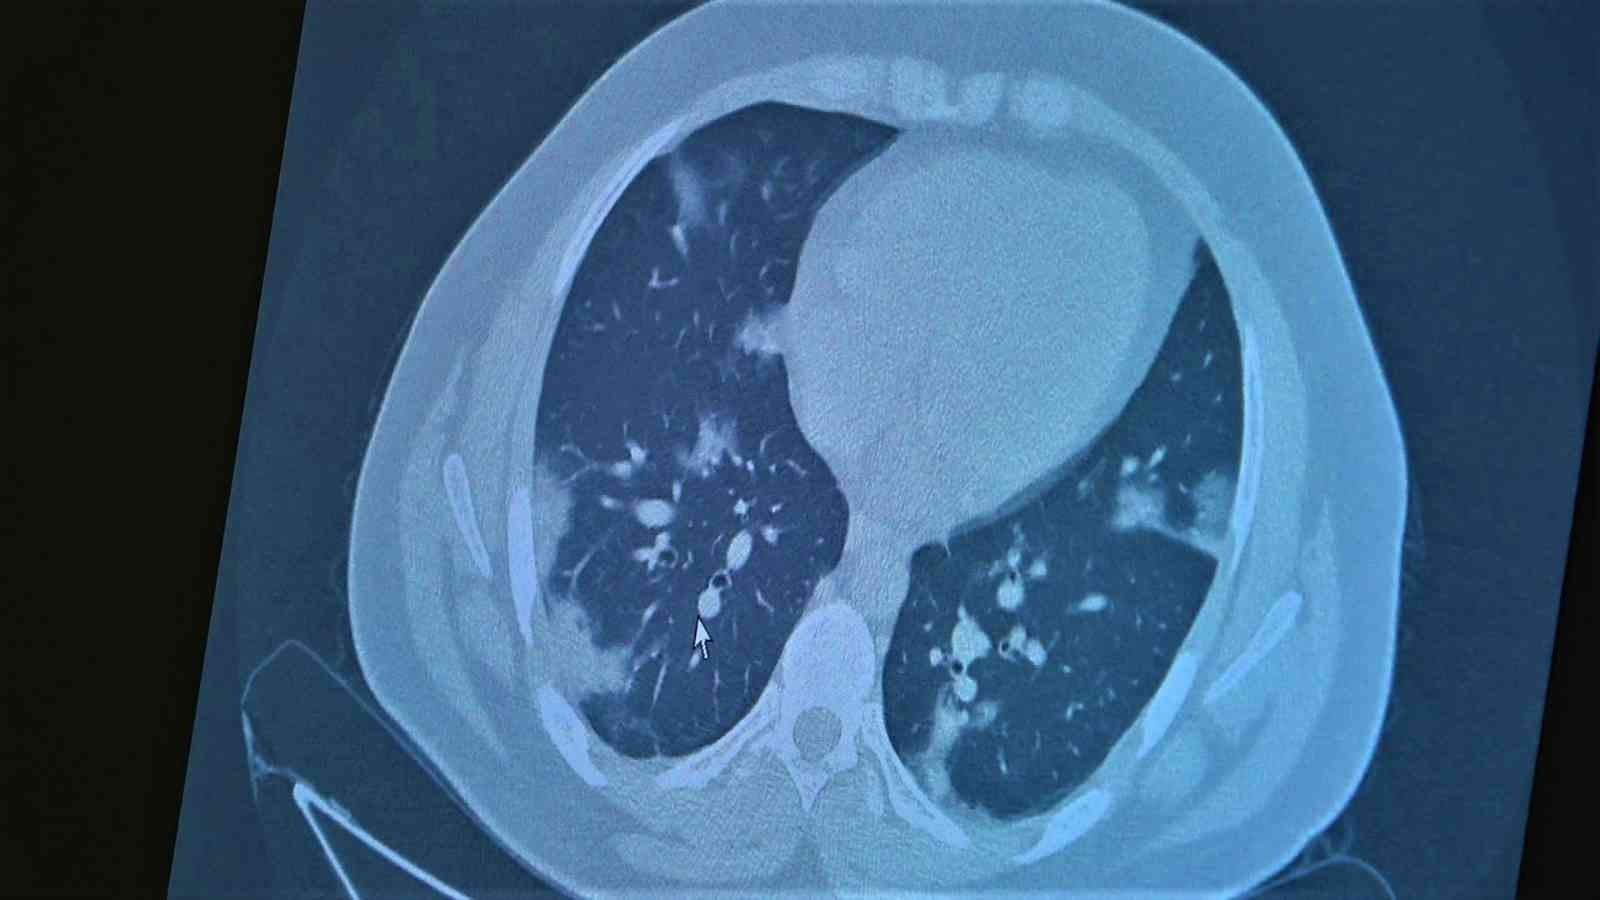

Korona virüsün mutasyona uğramış hali artık aşısız çocuklara ciddi zararlar vermeye başladığına dikkat çeken Göğüs Hastalıkları Uzm. Prof. Dr. Özkaya, 11 ve 14 yaşlarındaki koronaya yakalanmış ve ciddi akciğer tutulumlarıyla tedavi gören çocukların akciğer tomografilerini gözler önüne serdi.

Çocukların akciğer tomografilerini inceleyen Özkaya, "11 yaşında kovid pozitif bir öğrencimiz, yüksek ateş ve nefes darlığı ile bize geldi. Ciddi akciğer tutulumu var. Geçen yıl 'bu çocuklar hastalıktan etkilenmiyor' diyorduk. Bu çocukta görüyorsunuz buzlu camlar ve konsolidasyon alanlarla seyrediyor. Geçen yıl bu şekilde çok çocuk görmüyorduk. Önümüzdeki aylarda bu şekilde devam ederse çocuklarımızı kaybetmeye bile başlayabiliriz. 14 yaşında pozitif olan bir diğer çocuğumuz ise aşı randevusu almış ama aşısını olmadan ateş ve öksürükle başvurdu. Halen şanslıyız. Çocuklar tedaviye çok hızlı yanıt veriyor. Çekilen tomografisinde ise bilaterel yaygın tutulumları vardı. Bu ise 24 yaşında genç hastanın akciğer tomografisi. Bu kişide yaygın akciğer tutulumları görüldü. Bunu da tedavi ettik. Önümüzdeki aylarda ne getirecek ne götürecek beraber göreceğiz. Özellikle havaların soğumasıyla kapalı ortamlarda geçirilen zamanın ve kalabalıkların etkisiyle vaka sayılarının önümüzdeki günlerde artacağını biliyoruz. Şu an hastalık gerçekten 30-40 yaş altı gençlerde görülmeye başladı. Poliklinik şartlarında olanların büyük bir kısmı 30 yaş altı hastalar. Servislerde yatanlarda orta yaş ve altı nüfus. Yoğun bakımda yatanların büyük bir kısmı ise aşısız erişkin insanlardan oluşuyor" diye konuştu.